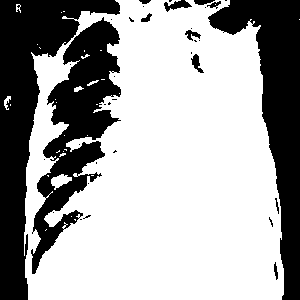

Threshold